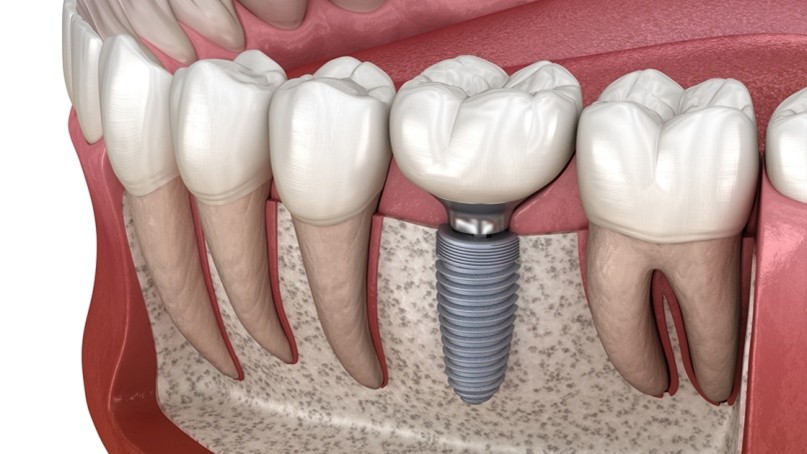

What Are Dental Implants?

Dental implants are artificial tooth roots made from biocompatible titanium that are placed into the jawbone to support replacement teeth such as crowns, bridges, or dentures. They look, feel, and function just like natural teeth.

Implants fuse with the jawbone through a process called osseointegration, making them extremely stable and durable. This is why implants are considered the gold standard for replacing missing teeth.